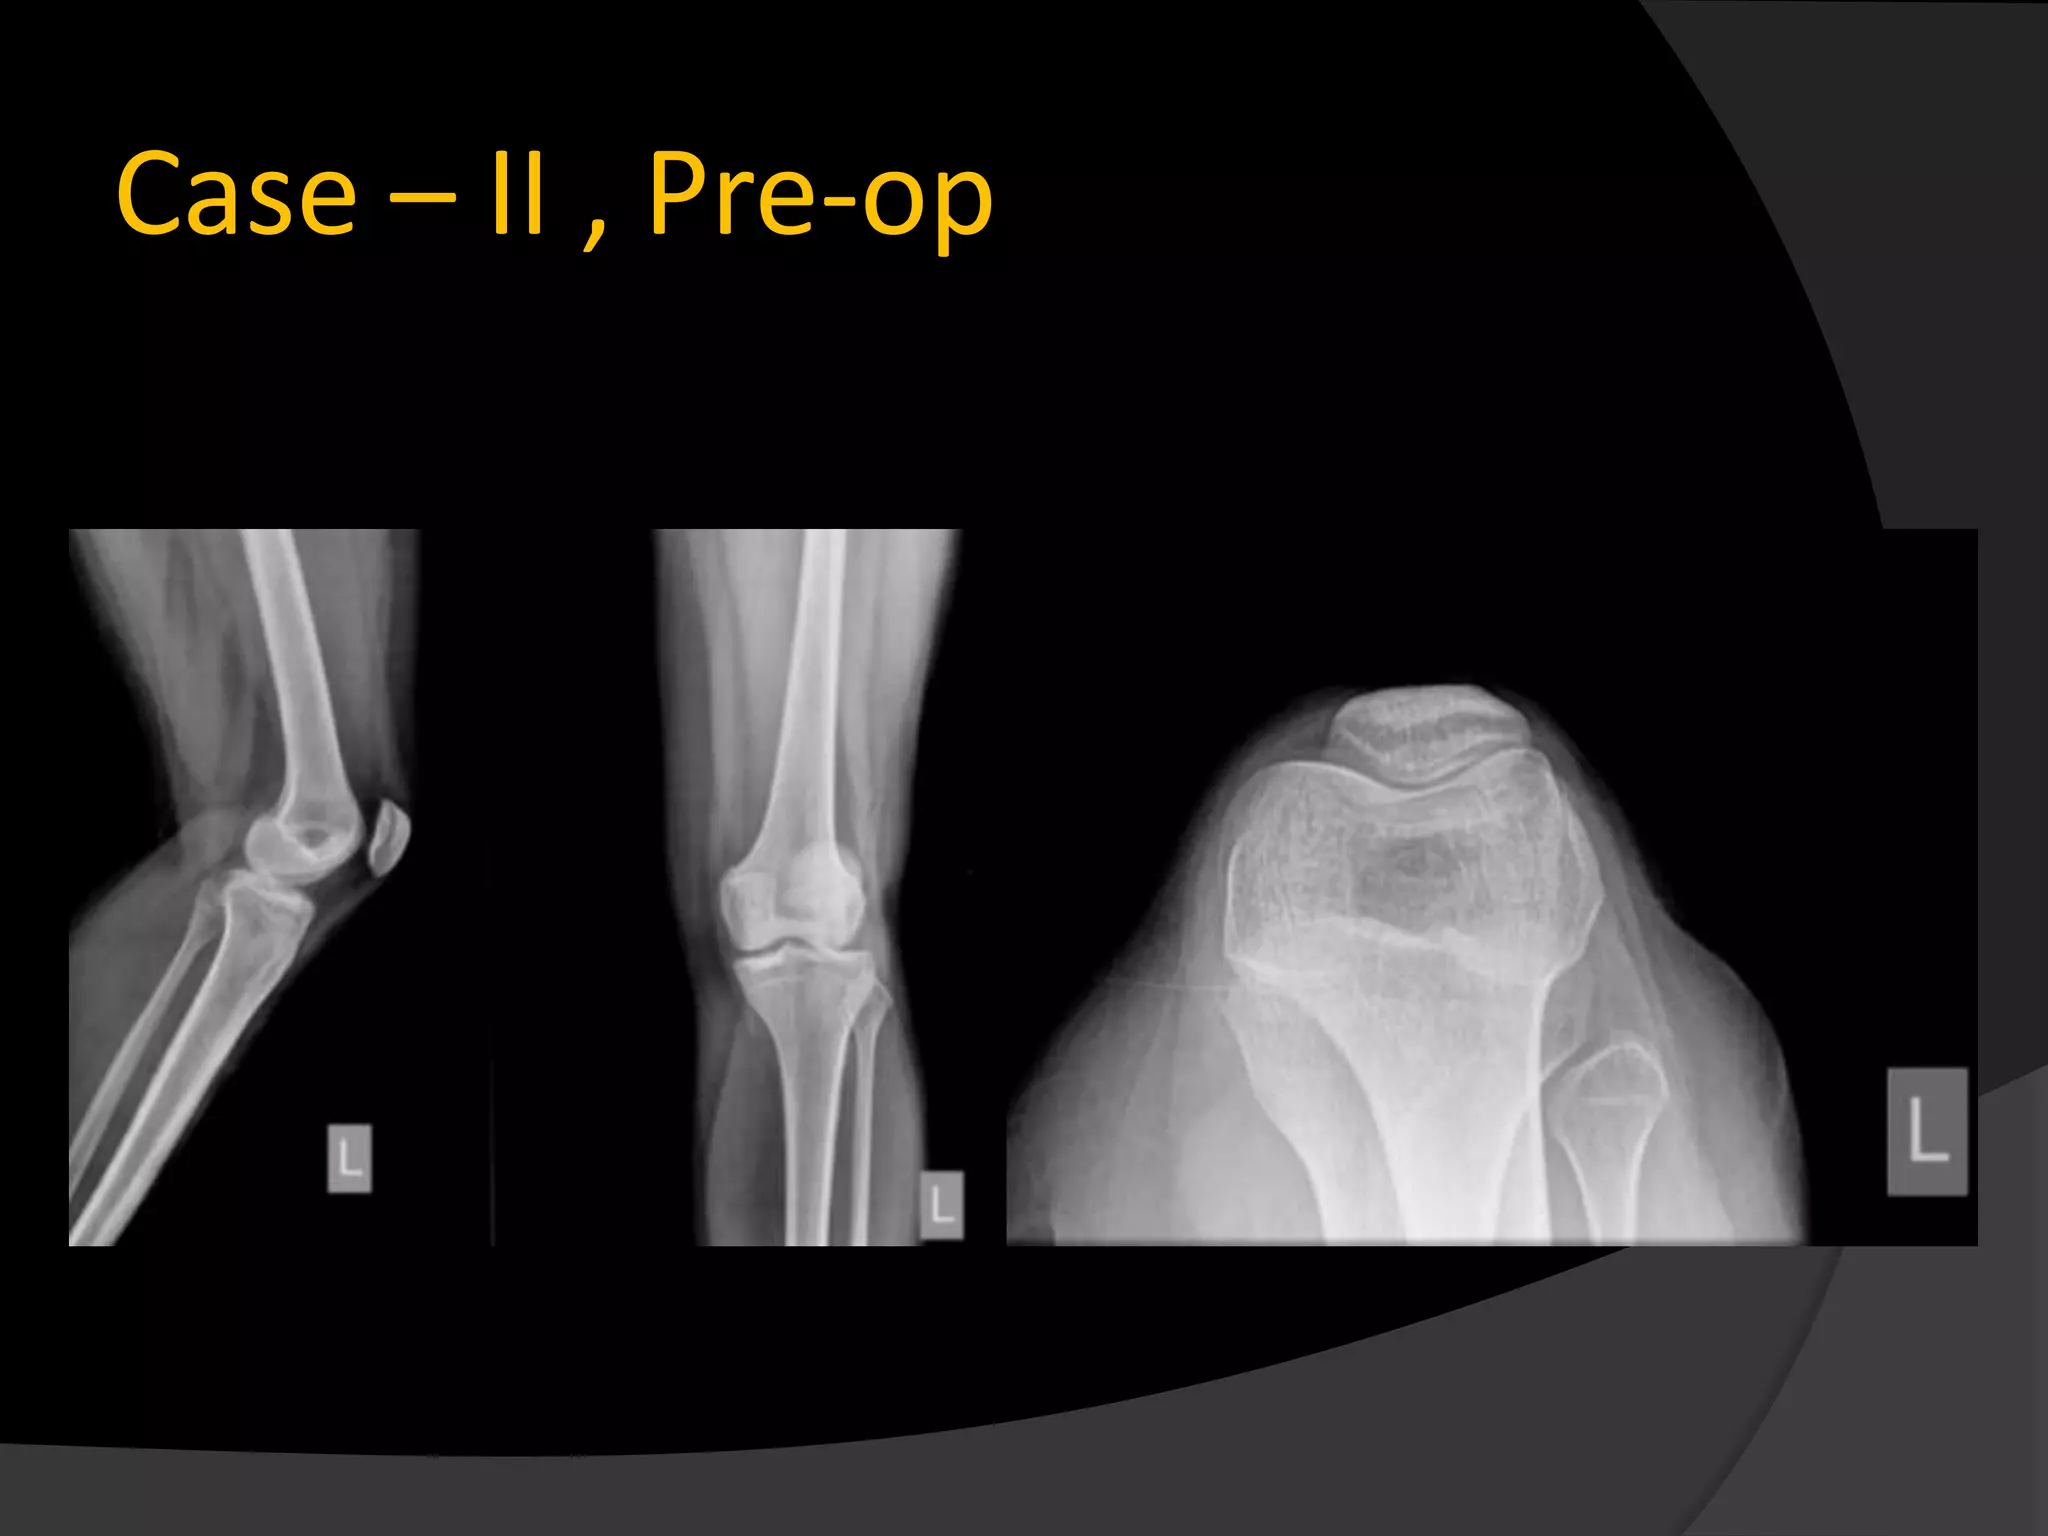

Case – II , Pre-op

Case – II, Pre-op